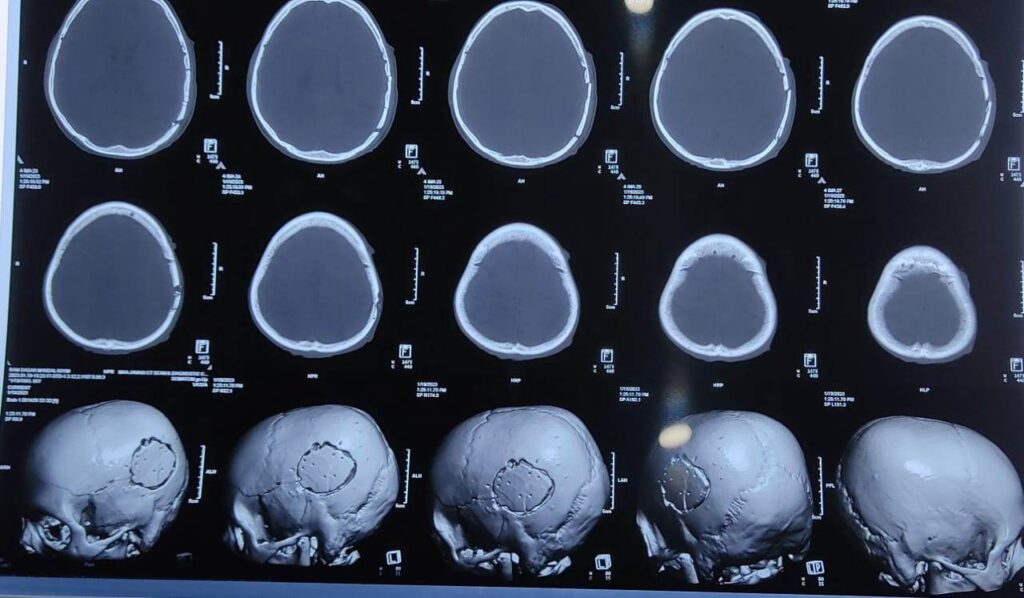

बच्चाहरुको सामान्य बिवादमा आरोपित भनिएका दिनेश मण्डलले हातमुक्काले हानेको र मुकेश मण्डलले टाउकोमा दाउरा चिरपटले प्रहार गर्दा वृद्व रामसागर मण्डलको बाँया पट्टीको खप्पड फुटेर र टाउकोको हडडी भाचेरले नशा च्यापिएको थियो । गम्भिर घाइते रामसागर मण्डलको जनकपुरधाम न्युरो हस्पिटलमा उपचार भईरहेको छ । उहाँको पुस ३० गते टाउको खोलेर अप्रेशन गरिएको छ ।

समयमा उपचार भएकोले ज्यान जोगिएको अन्यथा ब्रेन हेमरेज भई ज्यान जाने अवस्था रहेको चिकित्सकहरुले बताएको पीडितका छोरा रामप्रमेश मण्डलले बताउनुभयो । विरामीको टाउकोमा रगत जमेको थियो, उपचारमा कमी भएको भए ब्रेन ह्यामरेज हुने अवस्थाबाट रोकेको जनकपुर न्युरो होस्पिटलले जनाएको छ ।

विरामीको टाउकाको सिटि स्क्यान, घाउँ लागेको फोटोदेखे पछि धेरै प्रयास पश्चात मात्र माघ ९ गते मुद्दा दर्ता भएको थियो । माघ १० गते जिल्ला अदालतबाट पक्राउ पुर्जी जारी गराइ पक्राउ गरिने भनिएकोमा हालसम्म प्रहरीले आरोपितहरुलाई पक्राउ नगरेको पिडित परिवारको आरोप छ । यस घटनामा आरोपितलाई संरक्षण गर्ने कार्य इलाका प्रहरी कार्यालय ढल्केवरको इन्सपेक्टर सिंह र सइको मिलोमतो समेत रहेका आशंका पिडित परिवारको रहेको छ ।